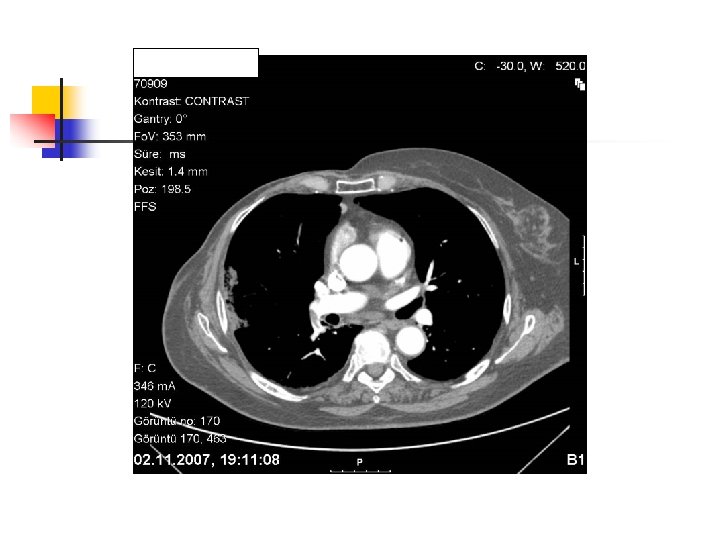

Spiral Computed Tomography Angiography (SCTA) n n n Allows rapid investigation of the pulmonary vasculature at peak contrast opasification within a single breath hold Three dimentional reconstruction is possible Sensitivity and specificity is around 90% up to subsegmental defects May demonstrate or exclude other abnormalities in the lung Bolus contrast is used for the visualization of the pulmonary vasculature Filling defects are diagnostic

Partial filling defect in right middle lobe and lover lobe artery Wedge shaped infiltration on the right upper lobe posterior segment